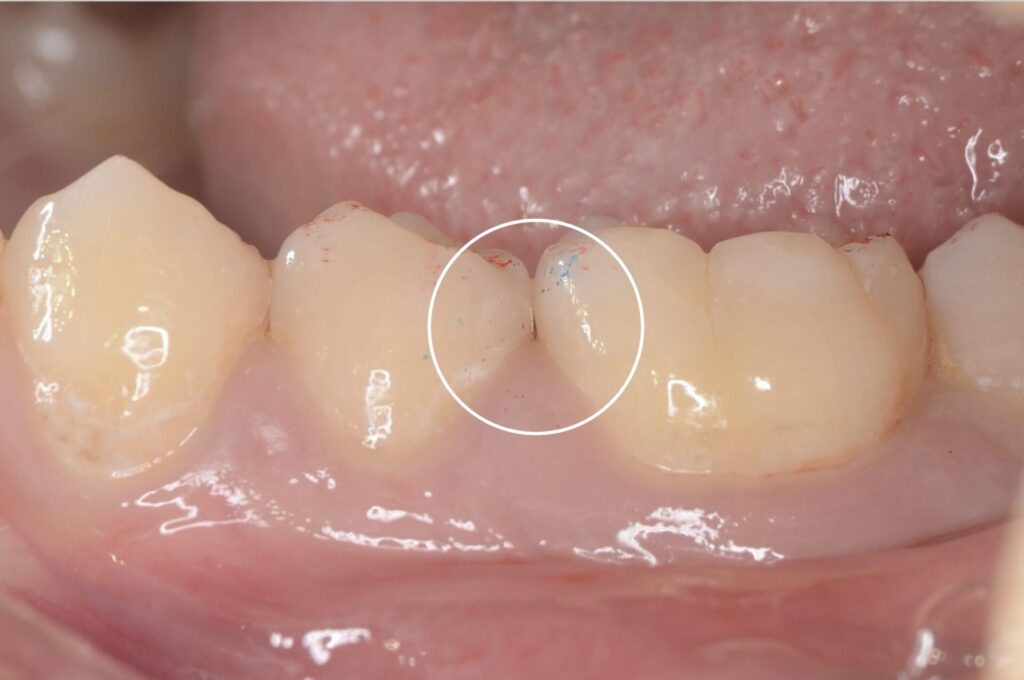

10代 虫歯治療 ダイレクトボンディング #60

Before

After

| 年齢 | 10代 | 治療方法 | ダイレクトボンディング |

| 性別 | 男性 | 通院回数 | 2回 |

| 主訴 | むし歯を治したい | 費用 | 55,000円(税込) |

| 治療のメリット | 歯を削る量を少なくできる・自然な見た目・境目がピッタリできる | ||

| 治療のデメリット | 大きい虫歯治療には適応できない場合がある | ||